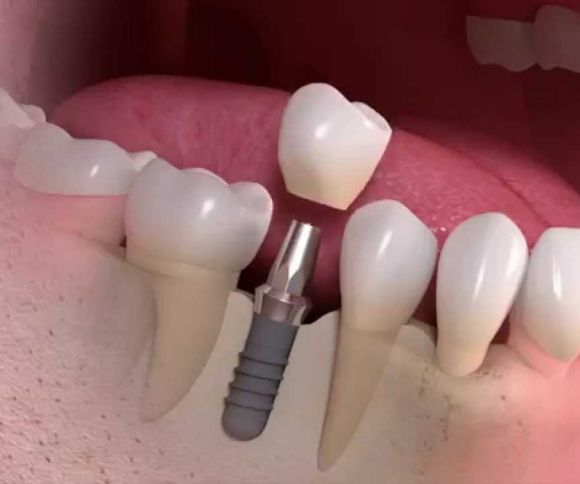

ডেন্টাল ইমপ্ল্যান্ট (Dental Implant)

• হারানো দাঁতের স্থানে প্রাকৃতিক দাঁতের মতো ইমপ্ল্যান্ট স্থাপন।

• টাইটানিয়াম ইমপ্ল্যান্ট ব্যবহার করে দাঁতের স্থায়ী সমাধান।